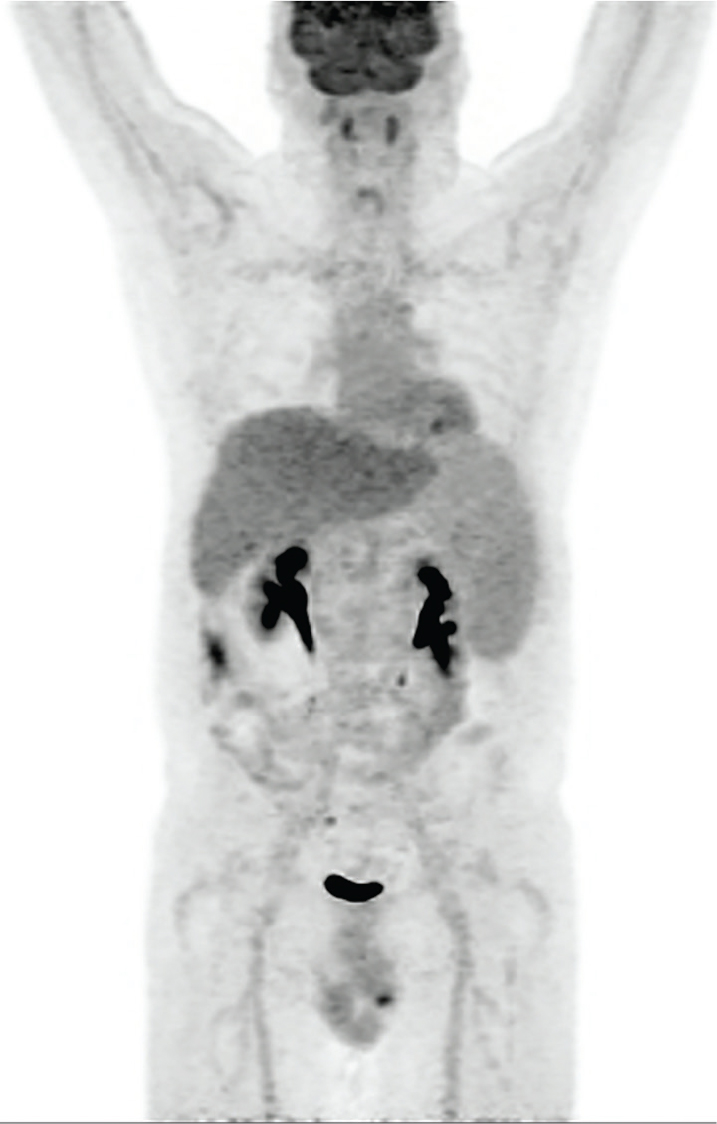

18F-FDG

Fig 3

Figure 3 Normal biodistribution of 18F-FDG, but with an enlarged spleen. Note the prominent brain activity, lower-level blood pool activity, more prominent liver activity and physiologic excretion along the urinary tract. Tonsillar, cardiac and bowel activity can be variable.